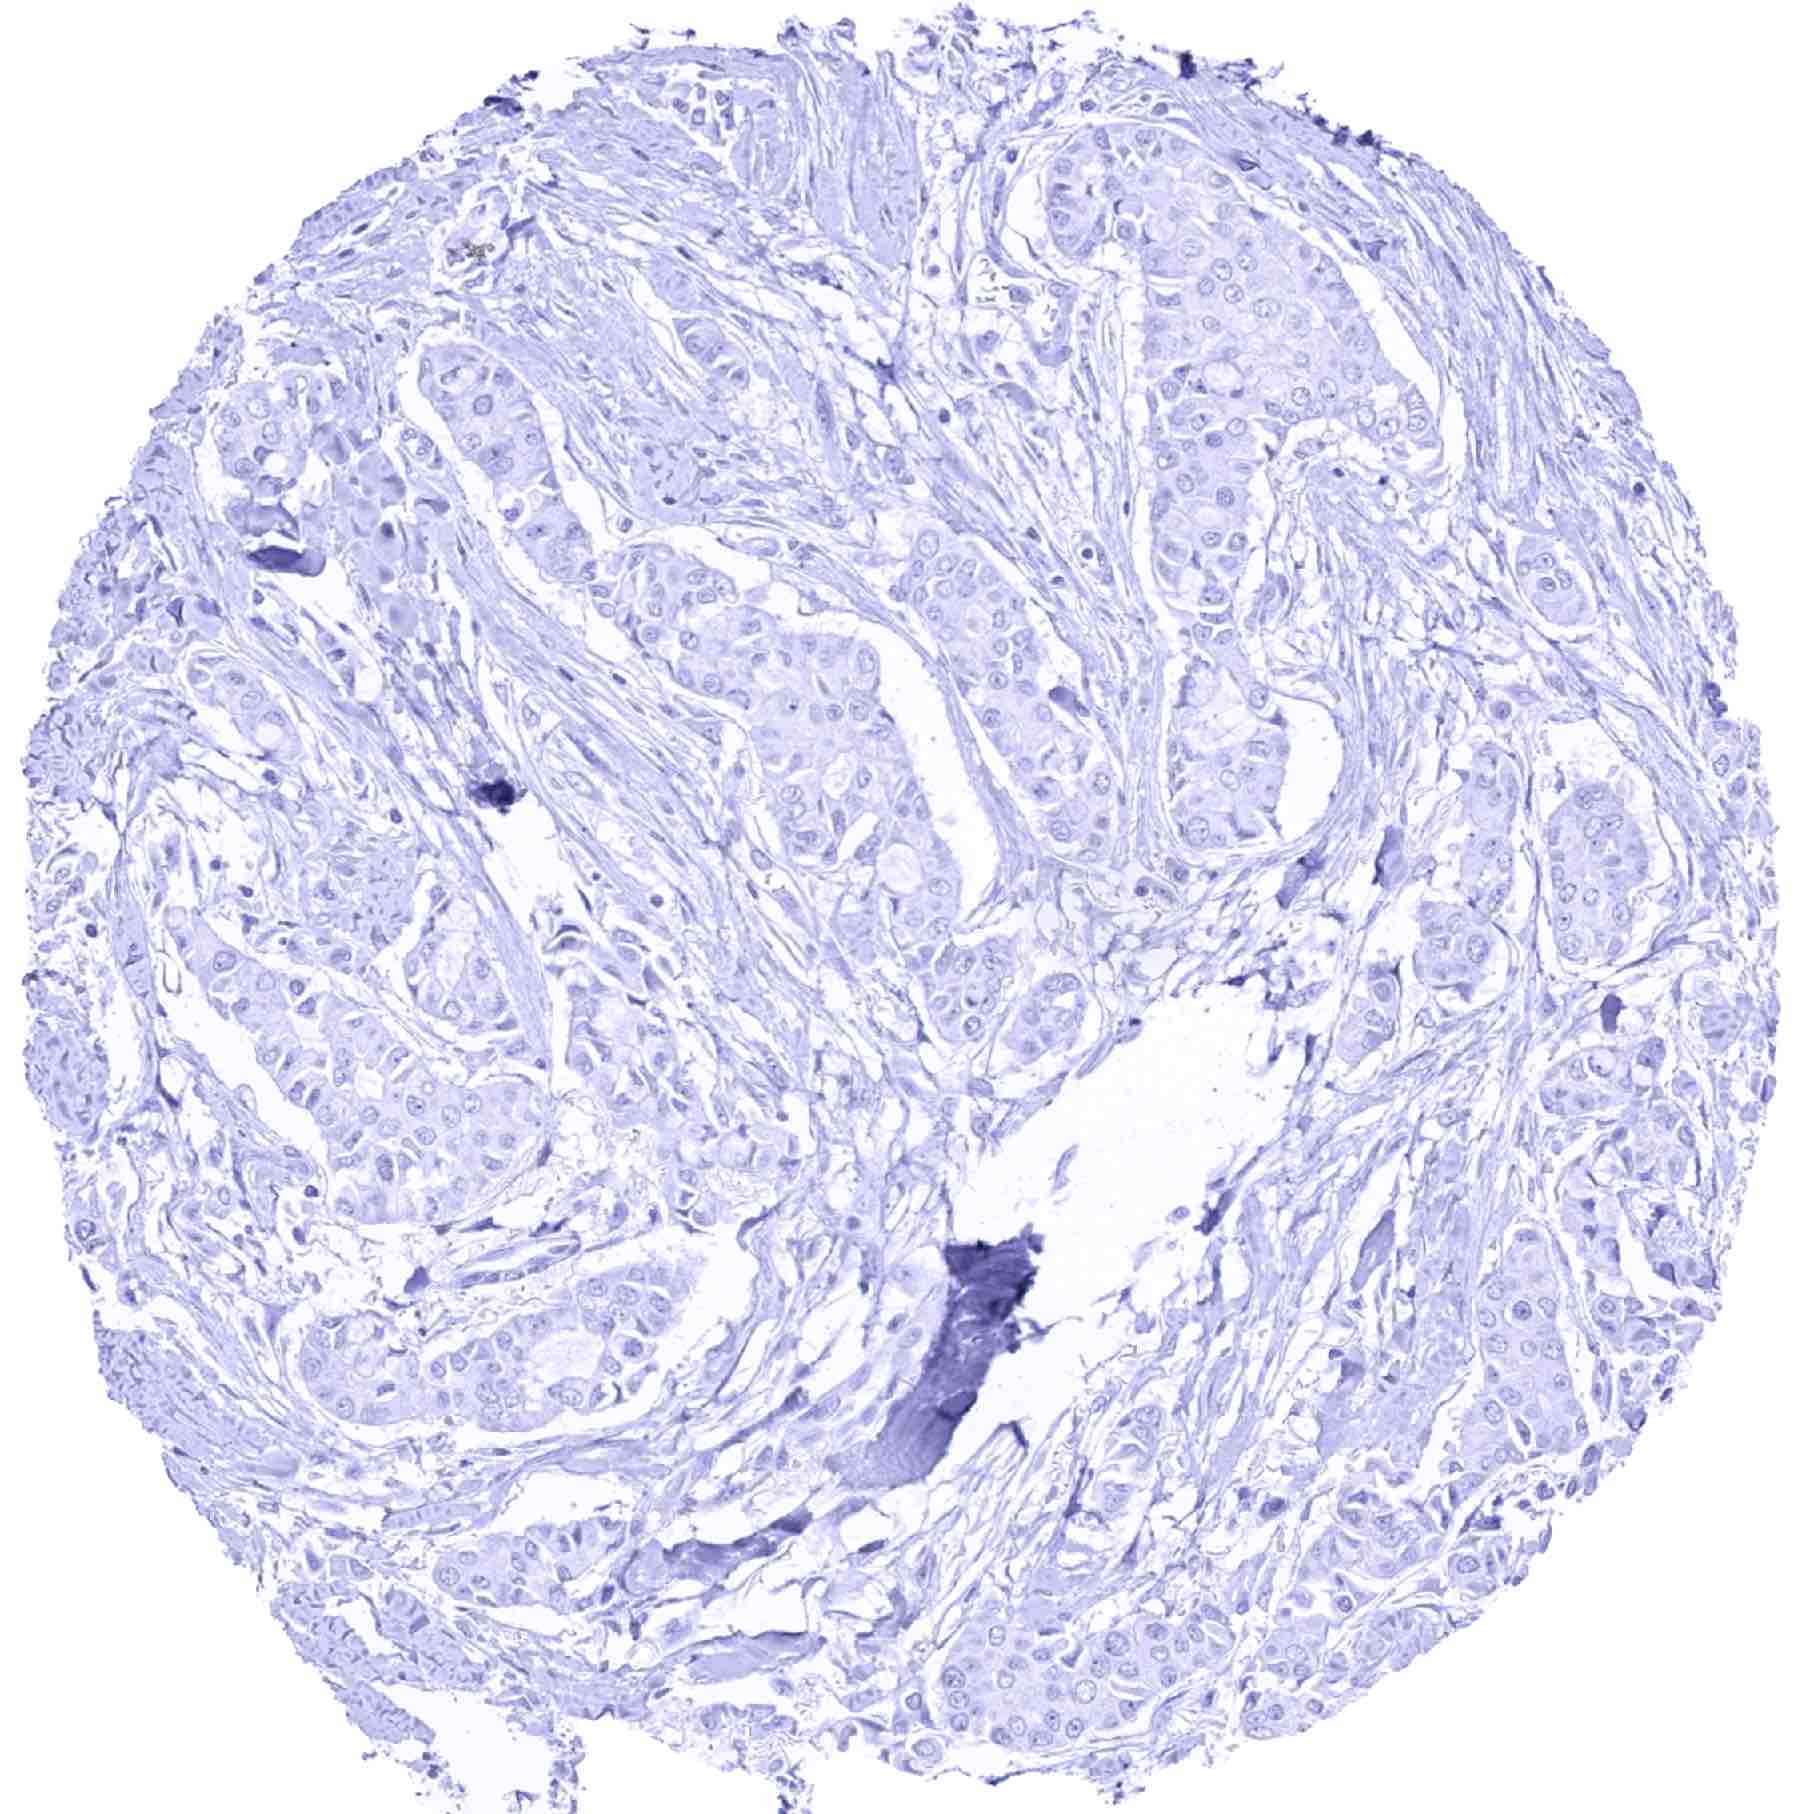

Prostate – Pepsinogen-I negative adenocarcinoma (Gleason 4+3=7)